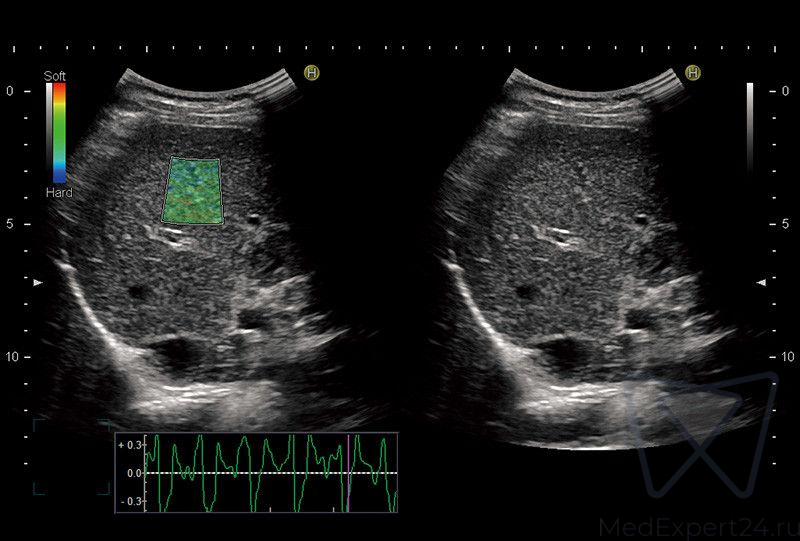

- HI-RTE эластография в режиме реального времени,